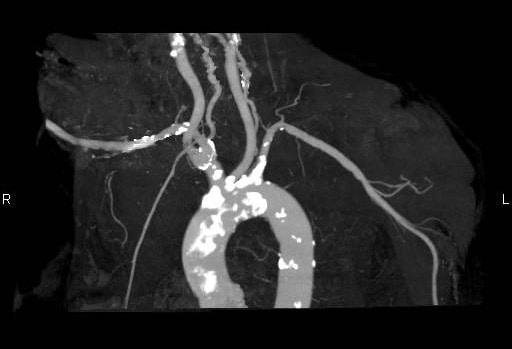

図4.胸部血管 VR (Volume Rendering) 画像 正面像

Bovine archを認める。

図5.胸部血管 VR (Volume Rendering) 画像 LAO 60°

左椎骨動脈の大動脈弓直接起始を認める。